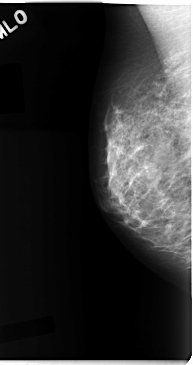

C_0090_1.RIGHT_CC

RIGHT_CC LINES 4712 PIXELS_PER_LINE 2592 BITS_PER_PIXEL 12 RESOLUTION 50 NON_OVERLAY